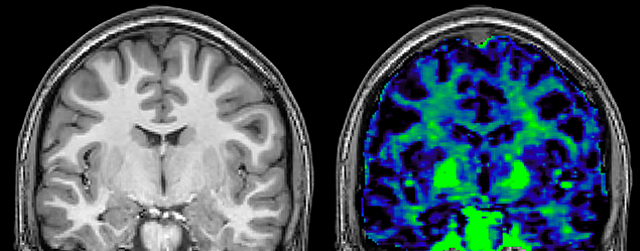

Myelin water imaging (MWI) is a breakthrough technique that was pioneered at UBC for measuring myelin content in the brain, in vivo. “Because the T2 time of water in myelin is much shorter than the T2 of water in the intraand extracellular spaces, we can separate out the myelin water signal.”

The techniques for measuring myelin have changed a lot over the years. “Since we are using the Elition, our myelin water images are much better. We're now acquiring 1 x 2 x 5 mm voxels and displaying at 1 x 1 x 2.5 mm. For a whole brain we can now measure the fraction of water in the myelin component in only about five or six minutes,” Dr. MacKay says.

of limiting MWI to the brain, even without the cerebellum, we can now spend about the same amount of time and scan the whole brain and the cervical spinal cord, which is a huge boost for us.” Dr. Rauscher says, “For MWI we perform 3D T2 with 32 or more echoes. This used to take a long time, but with Compressed SENSE we can decrease this to ten minutes for the whole head. Because of the large field of view (FOV) on the readout direction, we even get information from the brainstem, which we previously missed when we were using the GRASE approach. Having the whole head scan is nice because it has spatial resolution, orientation and FOV that are comparable to the standard 3D clinical MS scans, including the FLAIR and 3D T2, and a 3D T1 for brain volume.”

T1 - Weighted, Myelin Water Fraction Superimposed

Spinal cord coverage

Smaller, more isotropic voxels

Excellent detail in quantitative maps

Images courtesy of Adam Dvorak, Department of Physics and Astronomy, University of British Columbia